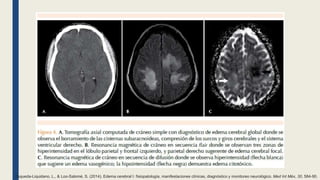

Esqueda-Liquidano, L., & Loo-Salomé, S. (2014). Edema cerebral I: fisiopatología, manifestaciones clínicas, diagnóstico y monitoreo neurológico. Med Int Méx, 30, 584-90.